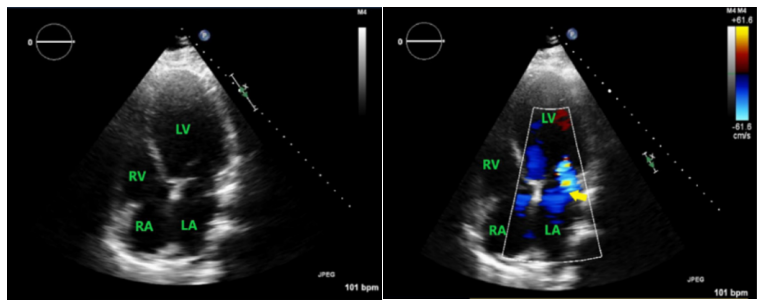

经超声心动图:双房大、左室大,二尖瓣中度返流,三尖瓣中度返流,心室厚度正常,严重左室功能障碍和弥漫性运动减退,左室射血分数严重减低(图2)。

图2 心脏彩超